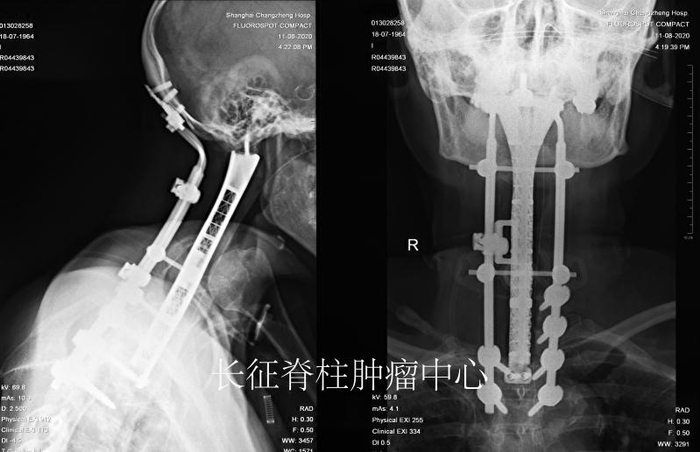

超长枕颈胸段切除重建一直是医学界悬而未决的世界性难题。近日,海军军医大学第二附属医院(上海长征医院)脊柱肿瘤中心肖建如教授团队为罹患颈胸椎巨大恶性脊索瘤的何女士,成功实施世界首例从颅底横跨颈椎,直通胸2椎体8椎节切除术,并为她安装3D打印人工寰枢胸椎复合假体及重建术,攻克了这一世界性难题。据悉,这是迄今全球最长节段颈胸段脊柱肿瘤切除术,也是自主研发最长跨度的3D打印人工寰枢胸椎复合假体。

手术如期进行,在麻醉科的全力配合下,肖建如、矫健团队在脊柱导航仪的辅助下,首先实施后路颈胸椎附件肿瘤切除术及枕颈胸内固定重建术。经过6个小时奋战,成功切除了颈1至胸1附件的肿瘤,并将左侧椎动脉从后方游离加以保护。

随后,根据患者的影像组学数据,团队自行设计出与患者全颈椎和胸椎的形态和长度相仿的3D打印“寰枢胸椎复合钛合金假体”,并通过动态力学模拟测试,运用于前方颅颈胸重建。接着,肖建如、矫健实施了二期前路颈胸椎肿瘤切除重建内固定术。经过4小时奋战,手术团队在3D鹰眼可视化高倍显微镜下彻底切除了寰枢椎至胸1椎体脊索瘤后,将定制的复合假体精准固定于患者颅底双侧枕骨髁和胸2椎体,并巧妙实现了前方复合假体与后路固定棒的前后链接。术后经呼吸科协助脱机训练,患者呼吸及脊髓神经功能逐渐改善,近期将转至康复医院继续治疗。